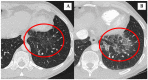

Conclusions: Lung and/or cardiovascular involvement were diagnosed in 15 (15.3%) patients in our historical cohort of patients with AIP type 1. Most of the lung involvement was presented in the form of nodular lesions in the lungs, non-specific infiltrates, "ground-glass" appearance with pleura thickening, and effusion. Aortic involvement was a major form of vascular involvement in patients with AIP, as in previous published studies on patients with IgG4-RD.